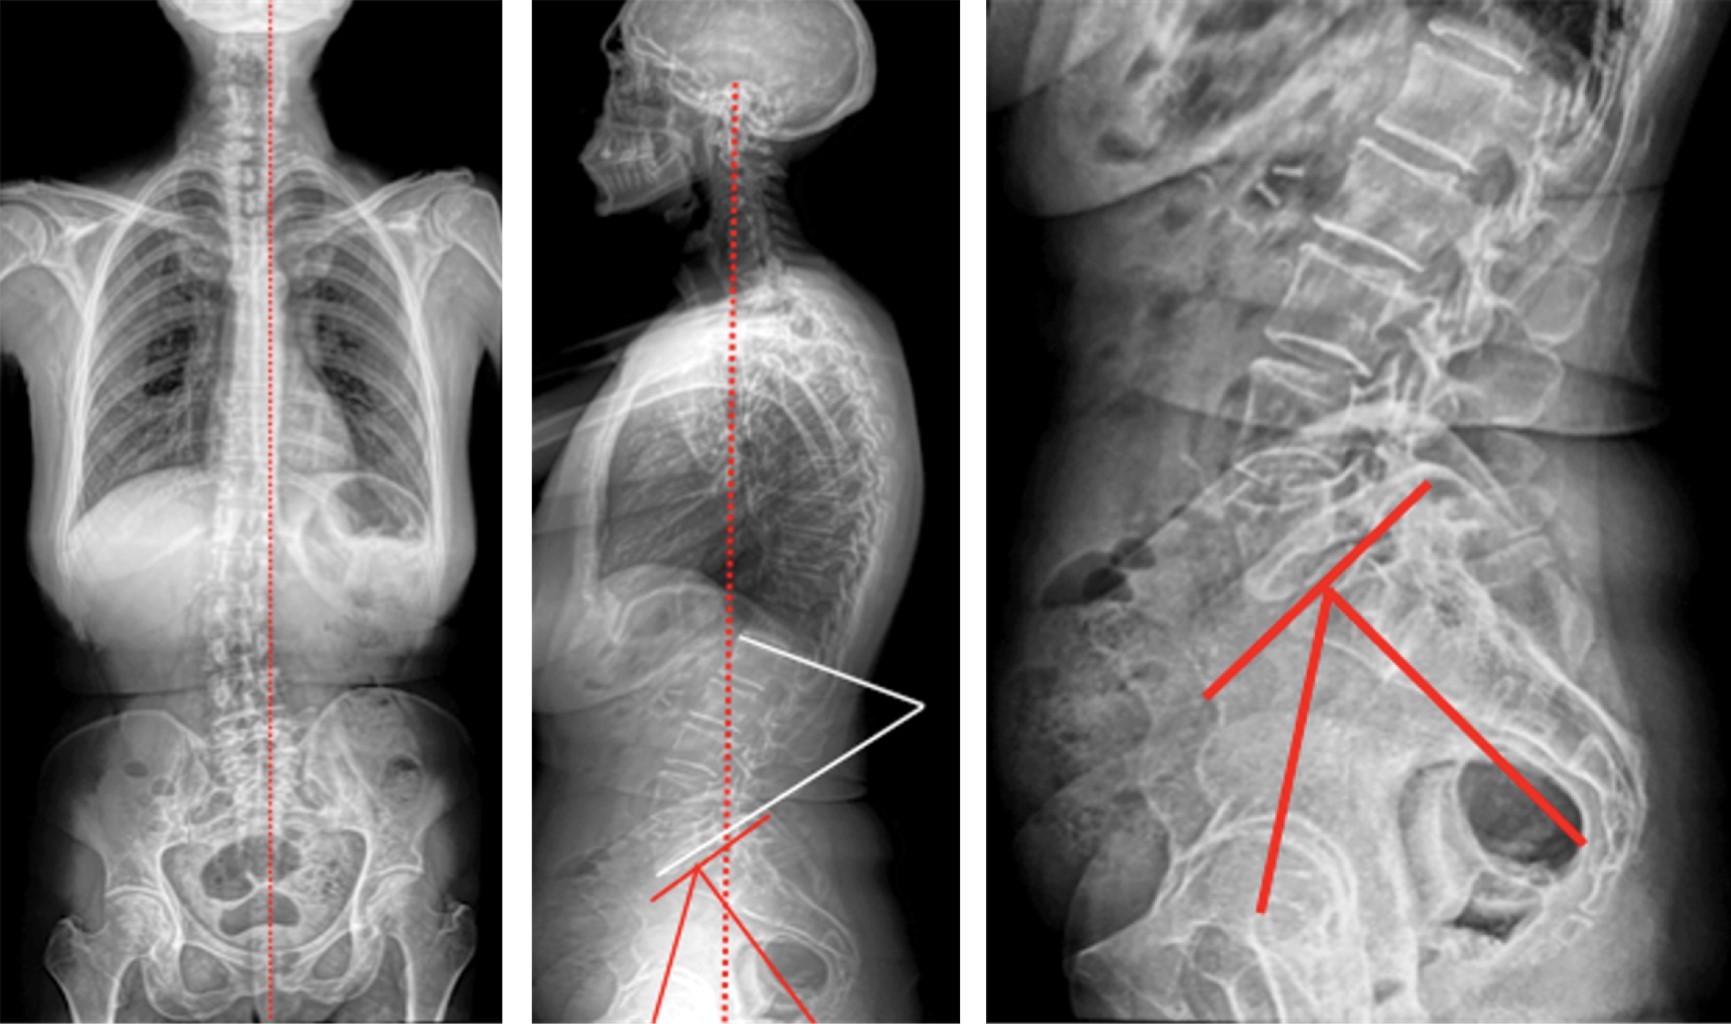

• 3. En pacientes en quienes se identifica patología espino-pélvica, indicar radiografías laterales de columna lumbosacra con el paciente de pie y sentado y aplicar las herramientas imagenológicas que se consideren convenientes, especialmente en aquellos con síndrome cadera-columna.

• 4. Aunque en esencia todas las mediciones tienen un componente dinámico, algunas son muy importantes para el tratamiento de las múltiples alteraciones vertebrales existentes y deben ser tomadas en cuenta en la planificación de una cirugía correctiva en la columna vertebral. Sin embargo, para un cirujano artroplástico de cadera, donde el foco de atención es, entre otros, determinar los riesgos de luxación, no es necesario aplicar todas las mediciones antes enunciadas, ya que es suficiente con determinar el plano anterior de la pelvis, el ángulo de la pendiente sacra, el índice de la relación sacro-pélvica, el ángulo de inclinación pélvica y la incidencia pélvica (Figura 19).

Figura 19